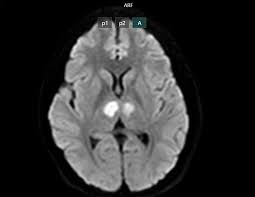

Cụ thể, khoảng 16h ngày 21/2 bệnh nhân vẫn nói chuyện với con, nhưng đến khoảng 19h30, gia đình phát hiện bệnh nhân trong trạng thái bất tỉnh, gọi hỏi không đáp ứng. Bệnh nhân không sốt, không co giật, không nôn. Người nhà đưa bệnh nhân đến bệnh viện tư để cấp cứu. Kết quả chụp MRI cho thấy não bệnh nhân có hình ảnh tổn thương vùng đồi thị hai bên. Gia đình xin chuyển bệnh nhân sang Bệnh viện Bạch Mai để được tiếp tục điều trị.